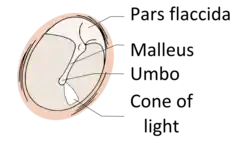

The eardrum is divided into two general regions: the pars flaccida and the pars tensa.[3] The relatively fragile pars flaccida lies above the lateral process of the malleus between the notch of Rivinus and the anterior and posterior malleal folds. Consisting of two layers and appearing slightly pinkish in hue, it is associated with Eustachian tube dysfunction and cholesteatomas.[4]

The larger pars tensa consists of three layers: skin, fibrous tissue, and mucosa. Its thick periphery forms a fibrocartilaginous ring called the annulus tympanicus or Gerlach's ligament.[5] while the central umbo tents inward at the level of the tip of malleus. The middle fibrous layer, containing radial, circular, and parabolic fibers, encloses the handle of malleus. Though comparatively robust, the pars tensa is the region more commonly associated with perforations.[6]

The manubrium (Latin: handle) of the malleus is firmly attached to the medial surface of the membrane as far as its center, drawing it toward the tympanic cavity. The lateral surface of the membrane is thus concave. The most depressed aspect of this concavity is termed the umbo (Latin: shield boss).[7]

When the eardrum is illuminated during a medical examination, a cone of light radiates from the tip of the malleus to the periphery in the anteroinferior quadrant, this is what is known clinically as 5 o'clock.